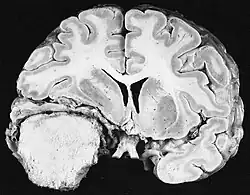

Les tumeurs primitives malignes du système nerveux central sont relativement rares et représentent environ 2 % de toutes les tumeurs malignes. Les maladies tumorales du système nerveux central sont distribuées à 95 % sur le cerveau et à 5 % sur les méninges, les nerfs crâniens et la moelle épinière. Ils peuvent survenir à tout âge et le risque de développer la maladie augmente avec l'âge. Chez l'adulte, les gliomes peuvent être retrouvés histologiquement à partir du tissu de soutien des cellules nerveuses, dont environ 75 % de glioblastomes Astrocytomes IV. degrés avec un pronostic défavorable. Les tumeurs embryonnaires prédominent chez les nourrissons et les jeunes enfants. En Allemagne, environ 3 970 personnes sont tombées malades en 2 016 hommes et 3 460 femmes atteintes de tumeurs malignes du système nerveux central. En moyenne, les taux de survie sont de 21 % pour les hommes et 24 % pour les femmes. Les statistiques incluent également rarement les tumeurs histologiquement bénignes du SNC, qui surviennent dans environ 6 000 nouveaux cas par mensonge de l'année. Environ 65 % provient des méninges. Les femmes sont beaucoup plus touchées. Si elles ne sont pas traitées par chirurgie ou radiothérapie, même les tumeurs bénignes peuvent être mortelles en raison de la croissance progressive dans l'espace crânien fermé. La tumeur maligne intracrânienne du SNC la plus fréquente est le glioblastome, la plus bénigne étant le méningiome.

Glioblastome

Les tumeurs des cellules gliales les plus courantes et les plus malignes sont les glioblastomes. Ils consistent en une masse hétérogène de cellules d'astrocytome peu différenciées principalement chez l'adulte. Ils surviennent généralement dans les hémisphères cérébraux, plus rarement dans le tronc cérébral ou la moelle épinière. Sauf dans de très rares cas, comme toutes les tumeurs cérébrales, elles ne s'étendent pas au-delà des structures du système nerveux central.

Le glioblastome peut provenir d'une forme diffuse (II. grade) ou un astrocytome anaplasique (III. grade) développer. Dans ce dernier cas, il est dit secondaire. Cependant, lorsqu'elle survient sans antécédent ni signe de malignité antérieure, on parle de maladie primaire. Les glioblastomes sont traités par chirurgie, radiothérapie et chimiothérapie. Ils sont difficiles à guérir et rares sont les cas qui survivent au-delà de trois ans.